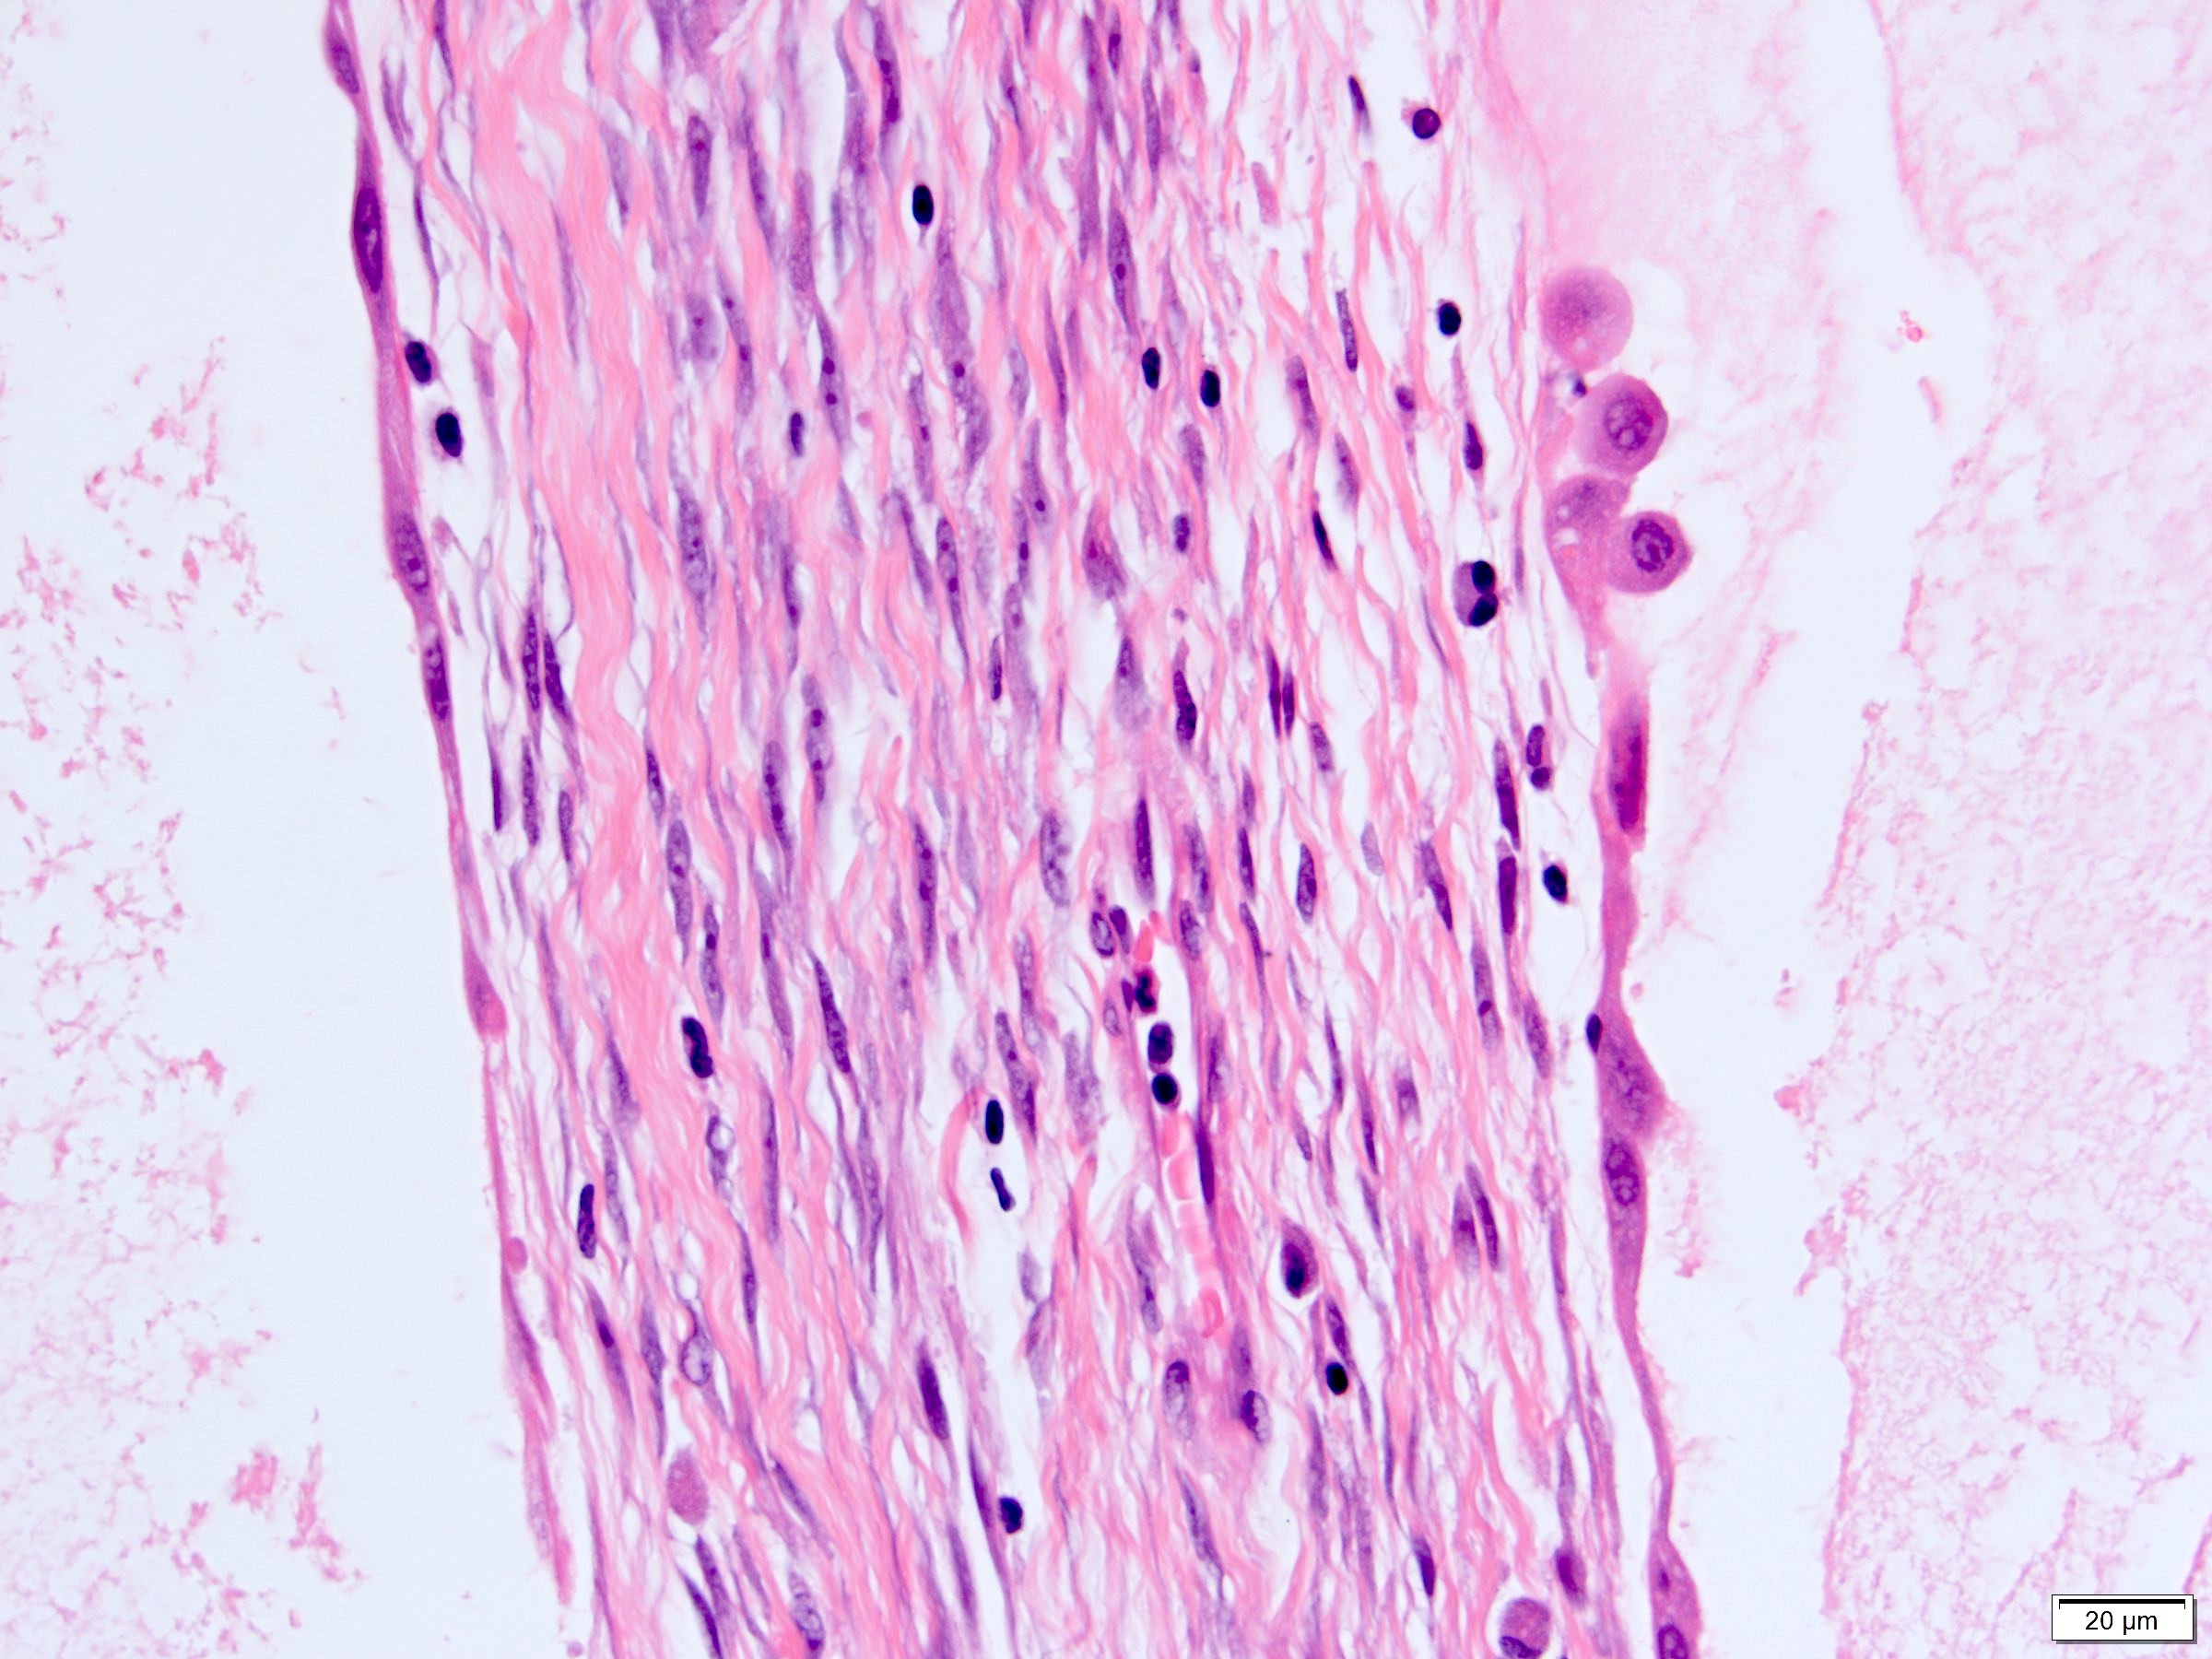

Microscopic (histologic) description

- Many with at least a partial pseudocapsule

- Entirely composed of cysts separated by septa (Semin Diagn Pathol 1998;15:2, Arch Pathol Lab Med 2004;128:1404, Am J Surg Pathol 2007;31:489, Eur Urol 2008;54:1237, Am J Surg Pathol 2016;40:1591)

- Stroma:

- Hypocellular to hypercellular

- Collagenous and fibrous to edematous and myxoid

- Areas of hyalinized stroma with contours resembling ovarian corpora albicantia

- Spindle cells; closely packed areas resemble ovarian stroma

- Cellular foci embedded with epithelial elements ranging from handful of cells with no lumen to tiny cysts with pinpoint lumens and to slightly larger cysts

- Steroidogenic cells: small clusters of polygonal cells with amphophilic cytoplasm and round nuclei, frequently around epithelial component

- Calcifications, multinucleated giant cells, foamy or hemosiderin laden macrophages and focal chronic inflammation

- Epithelium:

- Cells lining cysts

- Mostly arranged in single layer with various morphology: flat, cuboidal, hobnail, clear cell

- Rarely, foci of blunt and delicate papillae or foci of multiple layers of epithelium

- Minimal cytologic atypia

- Rare necrosis, no mitosis

Microscopic (histologic) images

A 6 cm predominantly well circumscribed, multicystic mass was incidentally found in a 55 year old woman. Sections of the partial nephrectomy showed the above histologic features. The stromal component is positive for ER and PR (shown above). What is the likely diagnosis?